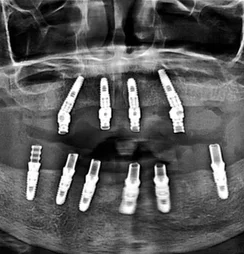

We employ digital x-rays and intraoral cameras for accurate diagnostics.